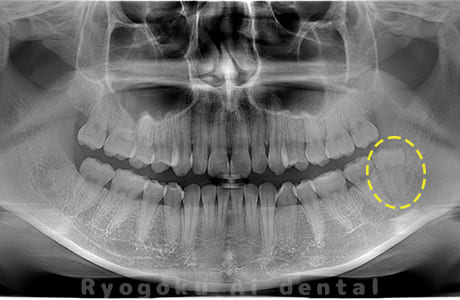

Case03

- 原因

- 上顎、下顎の親知らず

- 治療内容

- 上下4本の親知らずを抜歯したケースです。

<リスク・副作用>

手術後は痛み、腫れ、痺れなどの副作用が生じる場合があります。